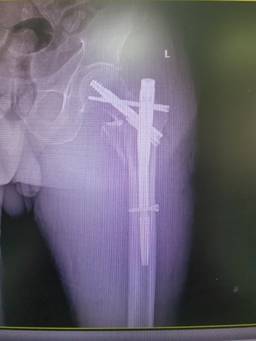

無(wú)獨(dú)有偶,石化醫(yī)院骨科隨后又收治了一位78歲左股骨轉(zhuǎn)子間骨折患者,團(tuán)隊(duì)再次自主完成高齡股骨轉(zhuǎn)子間骨折PFBN固定術(shù),術(shù)后患者恢復(fù)良好。

面對(duì)“人生最后一次骨折”,現(xiàn)在患者有了更好的選擇。據(jù)了解,目前PFBN技術(shù)在國(guó)內(nèi)開展屈指可數(shù)。此次石化醫(yī)院骨科2例手術(shù)的成功,填補(bǔ)了本地區(qū)該項(xiàng)技術(shù)的空白,也標(biāo)志著科室在老年髖部骨折微創(chuàng)手術(shù)領(lǐng)域又邁入了一個(gè)新的臺(tái)階。